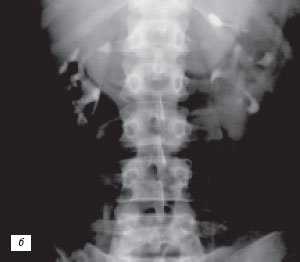

Многолетний опыт экскреторной урографии показал, что чашечно-лоханочные системы имеют крайне большое количество вариантов строения. Они практически индивидуальны не только для каждого человека, но и для левой и правой почек у одного субъекта. С развитием и все более широким использованием УЗИ и РКТ, позволяющим прослеживать как внутренние, так и наружные контуры паренхимы почек, на наш взгляд, аналогичное положение складывается и в отношении вариантов анатомического строения паренхимы почек. Сопоставление эхо- и компьютерно-томографических данных с урографическими при различных вариантах псевдоопухолей почек показало, что между анатомическим строением паренхимы и чашечно-лоханочных систем почек имеется взаимосвязь. Она выражается в конгруэнтности медиального контура паренхимы в эхо- или компьютерно-томографическом изображении с латеральным контуром чашечно-лоханочных систем, условно проведенным на экскреторных урограммах или на компьютерных томограммах с контрастным усилением [4, 17, 18]. Этот симптом прослеживается при обычном строении паренхимы и чашечно-лоханочных систем, а также при "перемычке" паренхимы почки, предсталяющей собой вариант анатомического строения. При опухоли почки, являющейся приобретенным патологическим процессом, конгруэнтность контуров паренхимы и чашечно-лоханочных систем почек нарушается (рис. 4).

Рис. 4. Симптом конгруэнтности контуров паренхимы и чашечно-лоханочной системы почки при неполной "перемычке" паренхимы (объяснение в тексте).